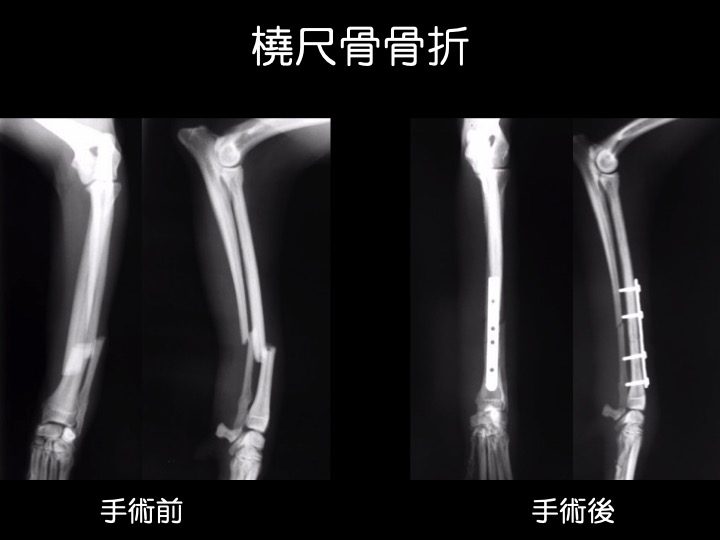

インプラント治療例

・小型犬(トイプードル、ポメラニアンなど)の前腕(橈骨、尺骨)は非常に細く、ソファやベッド、抱っこからの落下が原因で骨折するケースが多く見られます。

・骨折の治療は、ギプス、インプラントなどを用いて行われますが、これらはあくまでも、“骨折が治る=骨がくっつく” ための補助となるものです。

・骨折による骨のズレが大きい場合や、ギプス固定ができない箇所の骨折などが適応になります。

・骨折の部位、動物の大きさや手術用途にあわせて選択できるよう、様々な種類のものが作られています。